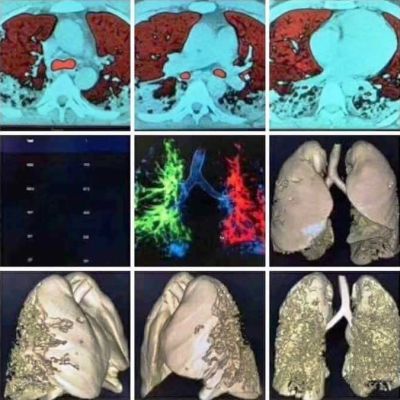

(Hình bên phải là chụp CT 2 lá phổi của một bệnh nhân bị nhiễm Covid-19, khi nó thâm nhập vào phổi thì nó ăn như bầy mối ăn gỗ tới mức mục rỗng và sẽ chết tức tưởi xảy ra. Covid-19 không đơn giản như cảm cúm, xin đừng xem thường nó mà hãy nhớ kỹ rằng, hiện nay trên thế giới chưa có thuốc nào khống chế được virus Covid-19)